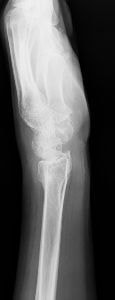

橈骨遠位端関節内粉砕骨折の術前(上)と術後(下)

橈骨遠位端骨折は、通年ですべての年齢層において最も多い上肢の骨折の一つです。骨折の主な原因は、転倒や高所から転落して手をつくことですが、手を強く捻って受傷することもあります。本骨折は、ケガの仕方、外力の大きさや骨の強さにより折れる場所や折れ方に様々なタイプ(型)があるのが特徴であり、尺骨や手根骨の骨折、手関節の靭帯損傷や神経障害を合併することもあります。

治療法は、骨折の型、骨折の徒手整復の可否、そして合併症の有無により異なり、比較的軽いものには保存的治療が、変形が大きかったり粉砕していたり骨折が関節内に及ぶ重症例には手術が行われてきました。しかしながら、近年は一人暮らしのご高齢の方の増加により、さほど重症でない骨折に対しても、早期から手の使用を可能とし、後遺障害を少なくするために手術を行うことが多くなってきています。

手術には、経皮的に鋼線を刺入して固定するピンニングや骨折部を直視下に整復してプレート固定する観血的手術があります。術後には早期の機能回復を目的としてリハビリ(作業療法)を行うことがあります。

大きな変形を残して骨が癒合すると手関節の疼痛や手指の機能障害が残存したり、将来、二次性の変形性関節症を生じる原因となることがあります。骨の変形による症状を改善させるために、矯正手術(骨切術)が必要になることがあります。